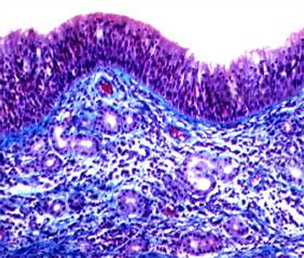

过敏性鼻炎即变应性鼻炎,是指特应性个体接触变应原后,主要由IgE介导的介质(主要是组胺)释放,并有多种免疫活性细胞和细胞因子等参与的鼻黏膜非感染性炎性疾病。其发生的必要条件有3个:特异性抗原即引起机体免疫反应的物质;特应性个体即所谓个体差异、过敏体质;特异性抗原与特应型个体二者相遇。变应性鼻炎是一个全球性健康问题,可导致许多疾病和劳动力丧失。